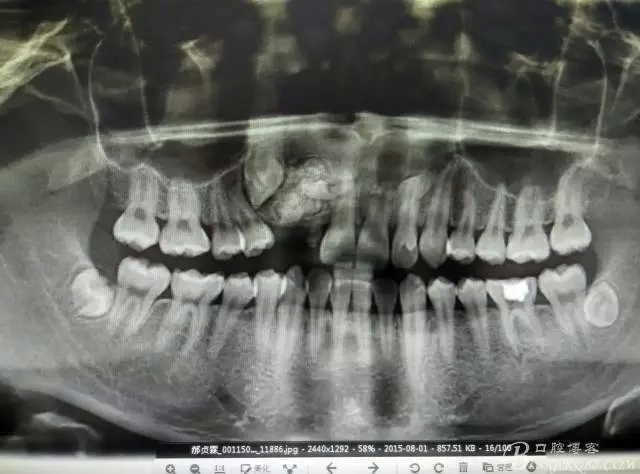

患者、郝xx、男、18歲,主訴:右側(cè)前牙未萌出,要求治療。專(zhuān)科檢查:右上乳Ⅱ滯留,牙冠變色,無(wú)松動(dòng)。12、13未見(jiàn)萌出。對(duì)側(cè)22、23正常萌出。缺牙區(qū)骨性隆起,表面不光滑,質(zhì)地堅(jiān)硬。范圍占有12、13區(qū)域。x全景片檢查:12、13阻生,其冠方有一團(tuán)2.5cmx1.8cm大小的致密團(tuán)塊,里面大小不等。不規(guī)則疑似牙齒影。診斷:牙瘤。處理:建議手術(shù) 摘除牙瘤。

圖2.全景片影像檢查:13阻生,其冠方有重疊影像,其冠方近中上方有一巨大致密鈣化團(tuán)塊。12看不見(jiàn)其蹤影。